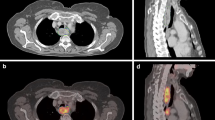

The results of the quantitative analyses are shown in Table 2 and Fig. 3. In 60% of patients the automatically segmented MTVs based on SUV ≥ 2.5 (MTV2.5) had to be edited manually, because they extended into surrounding organs (such as heart, kidneys or liver). The extension of the volume in the oesophagus or stomach was not edited, because tumour extension and oesophagitis or gastritis could not be distinguished.

Bland–Altman plot of maximum standardized uptake value (SUVmax) of the tumour (a), SUVmax of the most intense lymph node (b), MTV2.5 (c) and MTV50% (d) measurements on three-dimensional (3D) positron-emission tomography/computed tomography (PET/CT) and motion-compensated (MC) PET/CT. The x‑axis shows the mean of the measurement on 3D PET/CT and motion-compensated PET/CT and the y‑axis shows the difference between the measurements. The dotted lines show the mean differences (3D – MC) between both methods. The solid lines show the upper and lower 95% limits of agreement. (MTV2.5 metabolic tumour volume with SUV threshold of 2.5, MTV50% metabolic tumour volume with threshold 50% of SUVmax)

The primary oesophageal tumour showed a mean (95% CI) SUVmax of 13.1 (10.6–15.5) on 3D versus 13.0 (10.4–15.6) on motion-compensated PET/CT (p = 0.809). The most intense lymph node showed a mean (95% CI) SUVmax of 6.6 (4.3–8.8) on 3D versus 6.8 (4.6–9.1) on motion-compensated PET/CT (p = 0.176). MTV2.5s were not significantly different between 3D and motion-compensated PET/CT. Also, MTVs based on SUVmax ≥ 50% (MTV50%) were similar on both scans (p = 0.554). The Bland–Altman analysis showed mean differences between 3D and motion-compensated measurement (and corresponding 95% limits of agreement) of 0.08 (−3.60–3.75), −0.26 (−2.34–1.82), 4.66 (−29.61–38.92) cm3 and −0.95 (−19.9–18.0) cm3 for tumour SUVmax, lymph node SUVmax, MTV2.5, and MTV50%, respectively (Fig. 3). Percentage differences of 3D and motion-compensated MTV50% showed an interquartile range (IQR) of 92–109%. The two outliers (Figs. 3d and 4 and Supplementary Fig. 1D) were patients with a relatively low SUVmax (≤8) of the primary tumour, resulting in differences in MTV50% between −81% and +160% on the 3D and 4D scans.